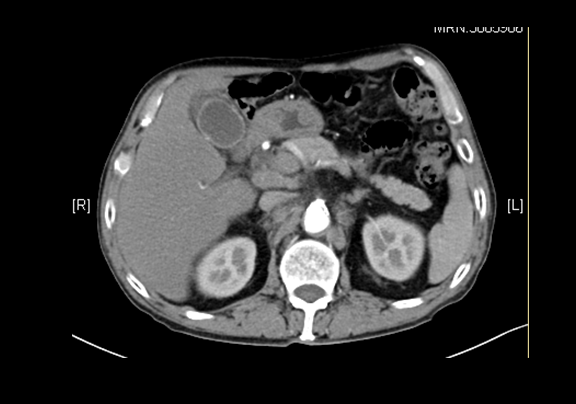

下腹部增强CT示:胆囊壁局限性不均匀增厚;疑似胆囊Ca;肝内外胆管扩张、肝左内叶类圆低密度影,感染性病变可能性大,肝左内叶类圆低密度影,暂不除外转移。

术前CT检查:

动脉期

静脉期